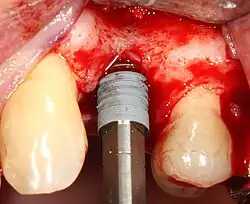

Placing the implant

Most implant systems have five basic steps for placement of each implant:[14]: 214–221

- Soft tissue reflection: An incision is made over the crest of bone, splitting the thicker attached gingiva roughly in half so that the final implant will have a thick band of tissue around it. The edges of tissue, each referred to as a flap, are pushed back to expose the bone. Flapless surgery is an alternate technique, where a small punch of tissue (the diameter of the implant) is removed for implant placement rather than raising flaps.

- Drilling at high speed: After reflecting the soft tissue, and using a surgical guide or stent as necessary, pilot holes are placed with precision drills at highly regulated speed to prevent burning or pressure necrosis of the bone.

- Drilling at low speed: The pilot hole is expanded by using progressively wider drills (typically between three and seven successive drilling steps, depending on implant width and length). Care is taken not to damage the osteoblast or bone cells by overheating. A cooling saline or water spray keeps the temperature low.

- Placement of the implant: The implant screw is placed and can be self-tapping;[31]: 100–102 otherwise, the prepared site is tapped with an implant analog. It is then screwed into place with a torque controlled wrench[35] at a precise torque so as not to overload the surrounding bone (overloaded bone can die, a condition called osteonecrosis, which may lead to failure of the implant to fully integrate or bond with the jawbone).

- Tissue adaptation: The gingiva is adapted around the entire implant to provide a thick band of healthy tissue around the healing abutment. In contrast, an implant can be "buried", where the top of the implant is sealed with a cover screw and the tissue is closed to completely cover it. A second procedure would then be required to uncover the implant at a later date.